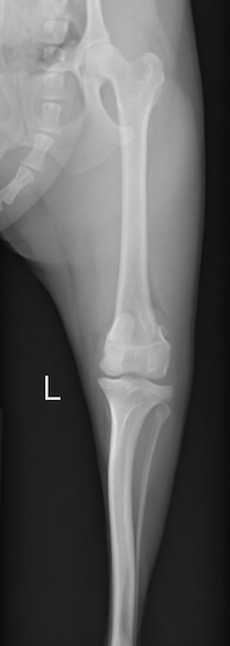

膝蓋骨が滑車溝の真ん中から左側(身体の内側)にずれているのが分かります

術後のX線画像です。膝蓋骨がきれいに滑車溝におさまるようになりました。